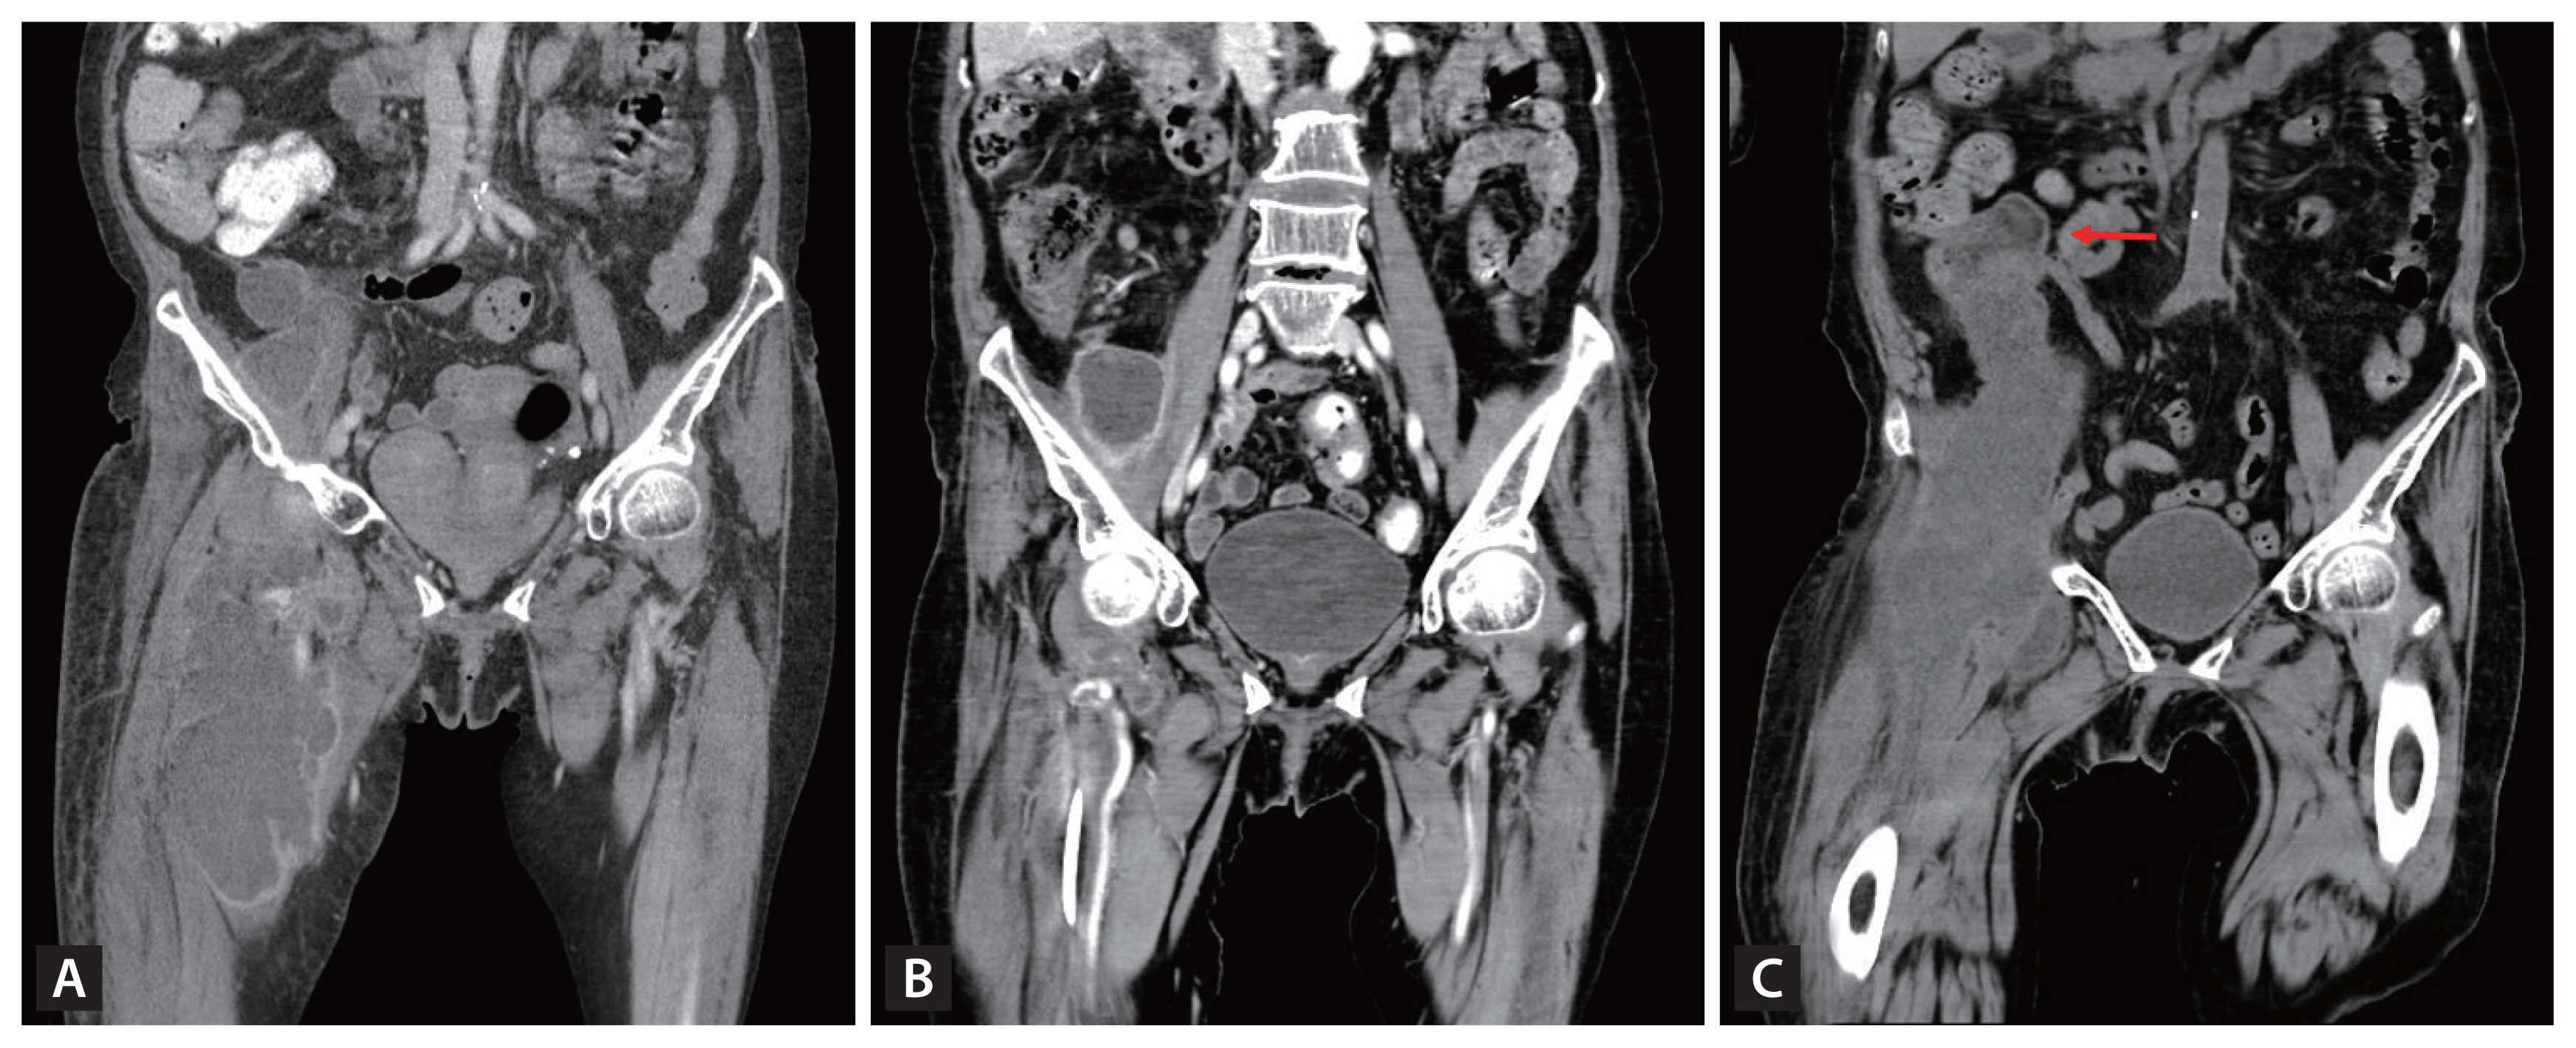

An unusual cause of a huge abscess in the thigh (1,644 times)

- Dae Gon Ryu, Su Bum Park, Cheol Woong Choi, et al.

-

Korean J Intern Med. 2024;39(3):537-538.

Image of interest

November 30, 2023